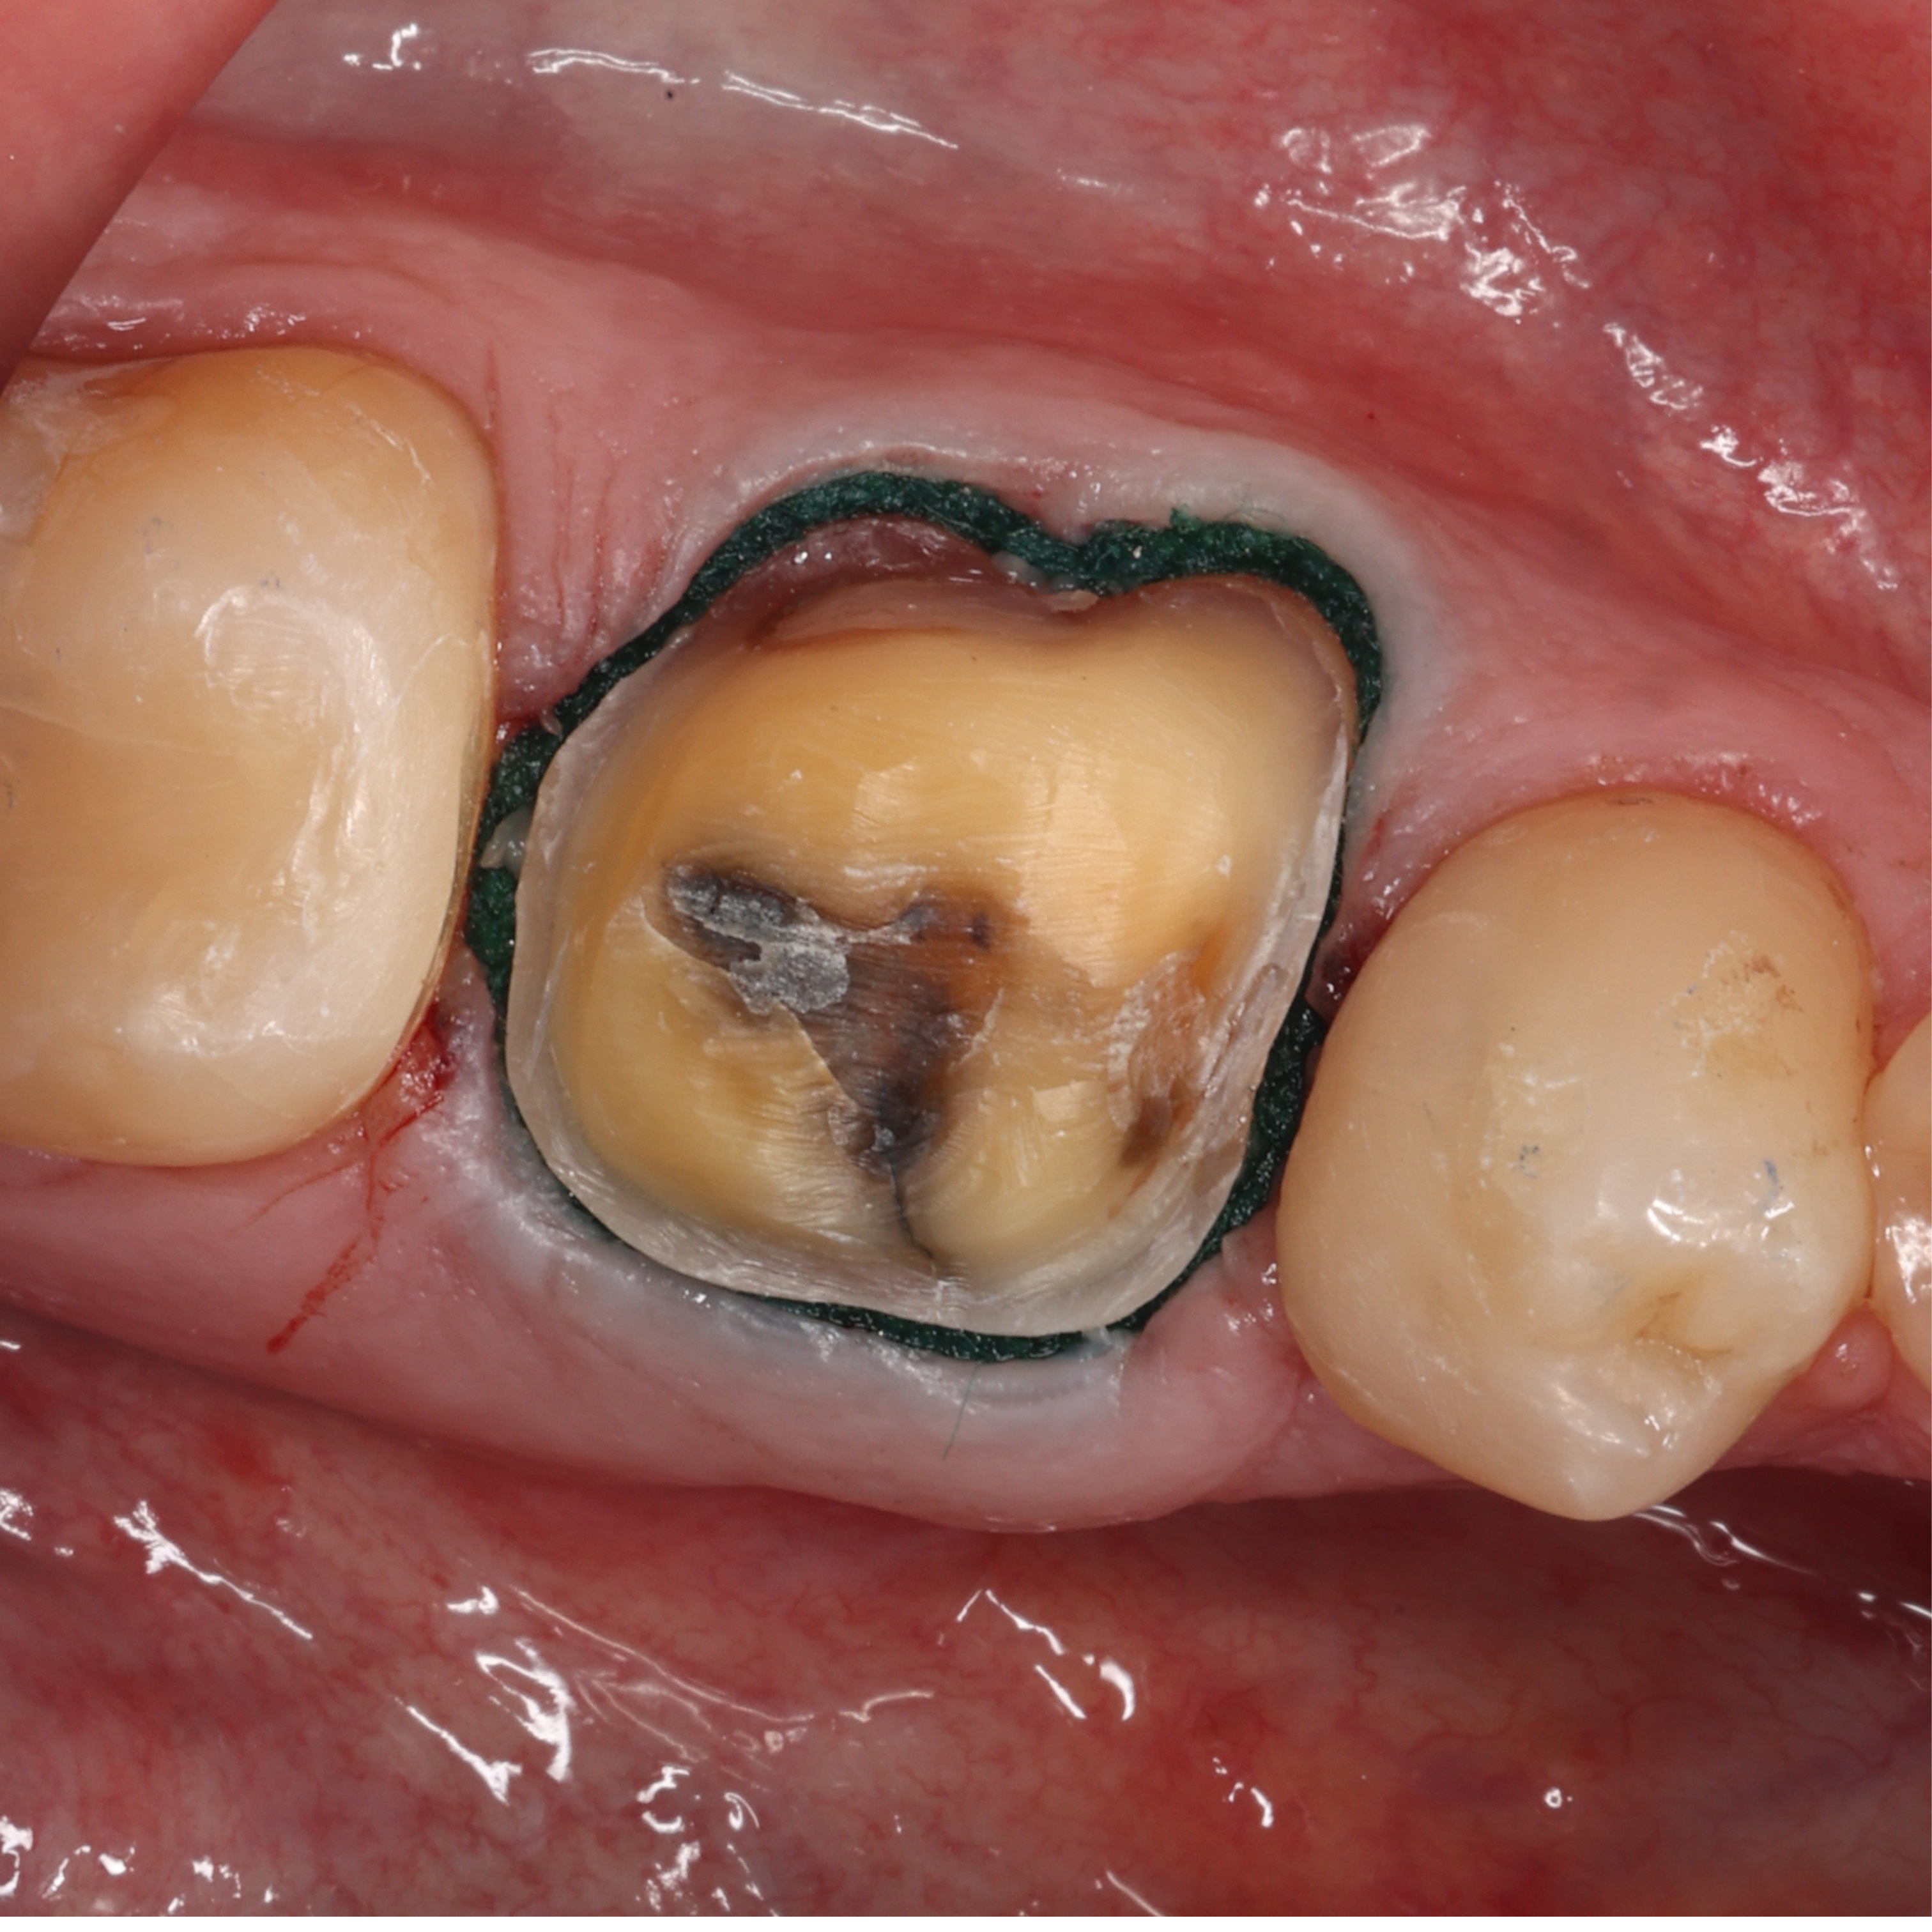

For the evaluation, I scanned the crown preparation of tooth #36 in the same patient with the following five scanners (Fig. 1) on the same day:

We can preview how these scanners capture colour (called texture) using the scanner’s native software. Every scanner captures colour slightly differently, depending on how accurately the scanner can pick up the light bouncing back off the prepared tooth and adjacent teeth. It also depends on the software algorithms that convert this data into colour (Fig. 2).

Colour scans of the same tooth preparation were captured using the five scanners and previewed in their native software. The TRIOS 5 scan was less bright (lower value) than the others (Fig. 3). Both the TRIOS 5 and Medit i900 scans were less warm in colour (hue) than the richer, warmer scans of Aoralscan 3, iTero Lumina and CEREC Primescan. The Aoralscan 3 scan appeared to be the most photorealistic in comparison. This type of scan texture is characteristic of many IOSs manufactured in China—whether you prefer realistic-looking capture of the intra-oral structures or a more illustrative representation is purely personal preference.

Monochromatic scans can also be taken and previewed in scanners’ native software. Scans in monochrome provide a better view of the preparation quality and are even recommended to check for any scan issues that are not as obvious when viewed in colour. Monochromatic scans of the same tooth preparation were captured using the five scanners and previewed in their native software. Unlike the native colour rendering, only two notable differences were evident between the five scans (Fig. 4). The iTero Lumina monochromatic scan was bright, almost overexposed, and the edges looked much sharper, almost jagged. The CEREC Primescan scan had slightly more definition of the occlusal morphology and the mesial and distal margins.

Figs. 3a–e: Processed colour scans of the same tooth preparation, previewed in the scanners’ native software. TRIOS 5 (a). Aoralscan 3 (b). Medit i900 (c). ITero Lumina (d). CEREC Primescan (e).

Figs. 4a–e: Processed monochromatic scans of the same tooth preparation, previewed in the scanners’ native software. TRIOS 5 (a). Aoralscan 3 (b). Medit i900 (c). ITero Lumina (d). CEREC Primescan (e).